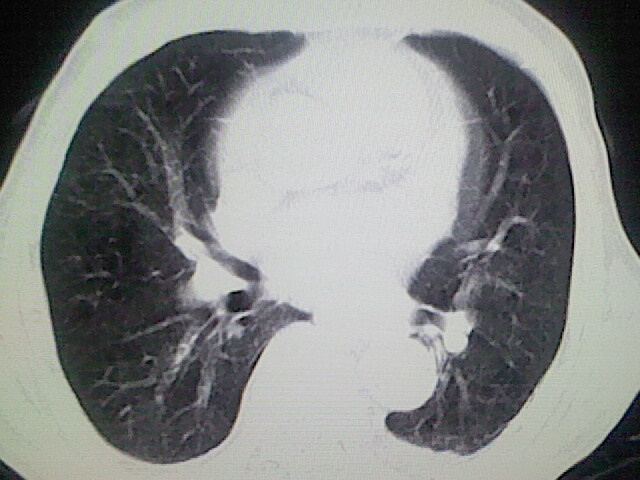

以下是引用zsl6918在2008-8-28 16:49:00的发言:[br]双肺炎性病灶,食管狭窄估计与心房增大压迫所致。

以下是引用xulianj在2008-8-28 20:36:00的发言:[br]慢支肺气肿伴感染,右上肺陈旧性结核;食道建议胃镜检查。

以下是引用wqs571018在2008-8-28 21:18:00的发言:[br]慢支继发感染,右上肺陈旧性结核;食道建议胃镜检查。